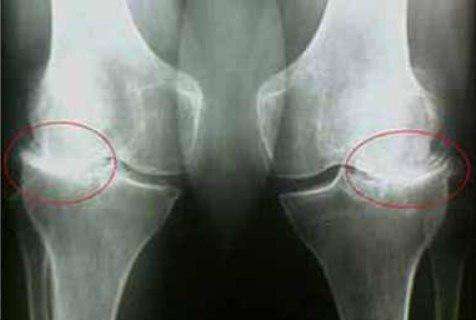

35-η

μέρα:έκανα εξετάσεις και ακτινογραφία του ώμου και του αγκώνα. Δεν υπάρχουν ίχνη αρθρώσεων! Ο

χόνδρος στις αρθρώσεις είναι σαν ενός νεαρού 30 ετών. Ο γιατρός είπε ότι στην προηγούμενη ακτινογραφία

υπήρχε πιθανότατα ένα ελάττωμα, οπότε η διάγνωση της οστεοαρθρίτιδας ήταν εσφαλμένη.

διαφορά:

πόδι μου. Ο πατέρας μου μου έφερε από κάπου το και Curcumactiv Δόξα το Θεό! Δείτε την διαφορά: